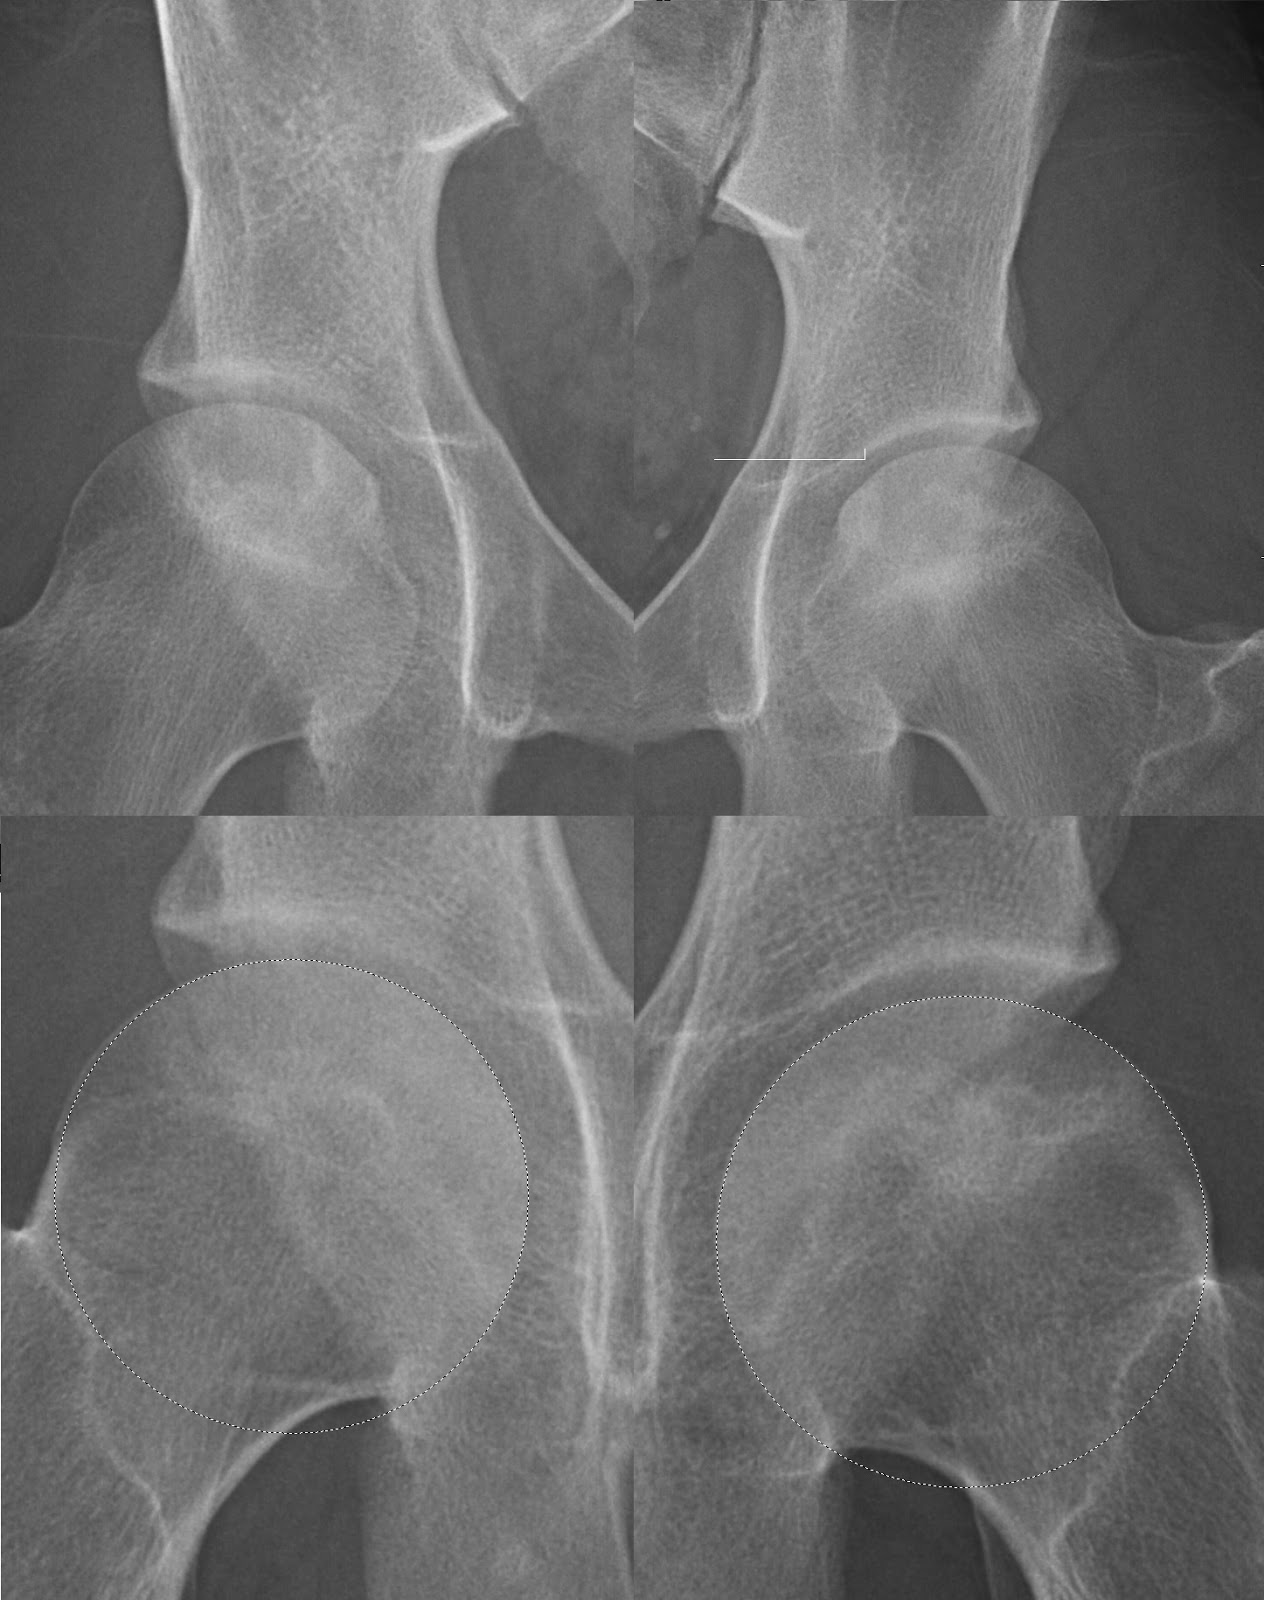

과거 Ficat stage 표를 보게되면

0단계를 따로 나누기도 하지만 0~1단계는 거의 정상인 상태,

2단계 부터는 뼈가 누르는 압력등으로 인해 '골경화'가 시작되는 상태입니다. Pre-collapse 라고 불리우기도 합니다.

3단계 부터는 뼈가 누르는 압력으로 인해 Crescent sign 이 보이는 시기입니다.

4단계는 변형이 너무 심해 2차적인 관절염이 생깁니다.

1단계는 MRI를 꼭 확인해서 골부종이 있는지 확인을 해보아야 하고

엑스레이에서는 2단계부터 확인을 할 수가 있습니다.

2B 부터 초승달 모양의 Crescent sign 이 확인되며

3단계부터는 골두의 심한 변형이 동반되어 보행시 절뚝거림이 시작될 수 있습니다.

4단계는 비구까지 영향을 준 상태로 인공관절 치환술이 필요할 수 있습니다.